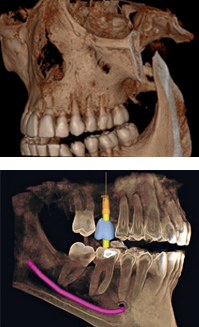

A TCCB representa um grande avanço na área de imaginologia e difere da radiografia convencional, pois permite a visualização tridimensional das estruturas ampliando as possibilidades de diagnóstico. É indicada para todas as áreas da odontologia, como para planejamento de implantes, localização de dentes inclusos, analise de canais radiculares entre muitas outras. A dose de radiação é muito reduzida, dado que trabalha com miliamperagens baixas, principalmente quando comparada com a tomografia computadorizada medica. Na Doc Ideal trabalhamos com tomógrafos de FOV 8x8 cm que adquirem toda a arcada dentaria e voxel de 0,1 mm que permitem uma qualidade de imagem muito superior.